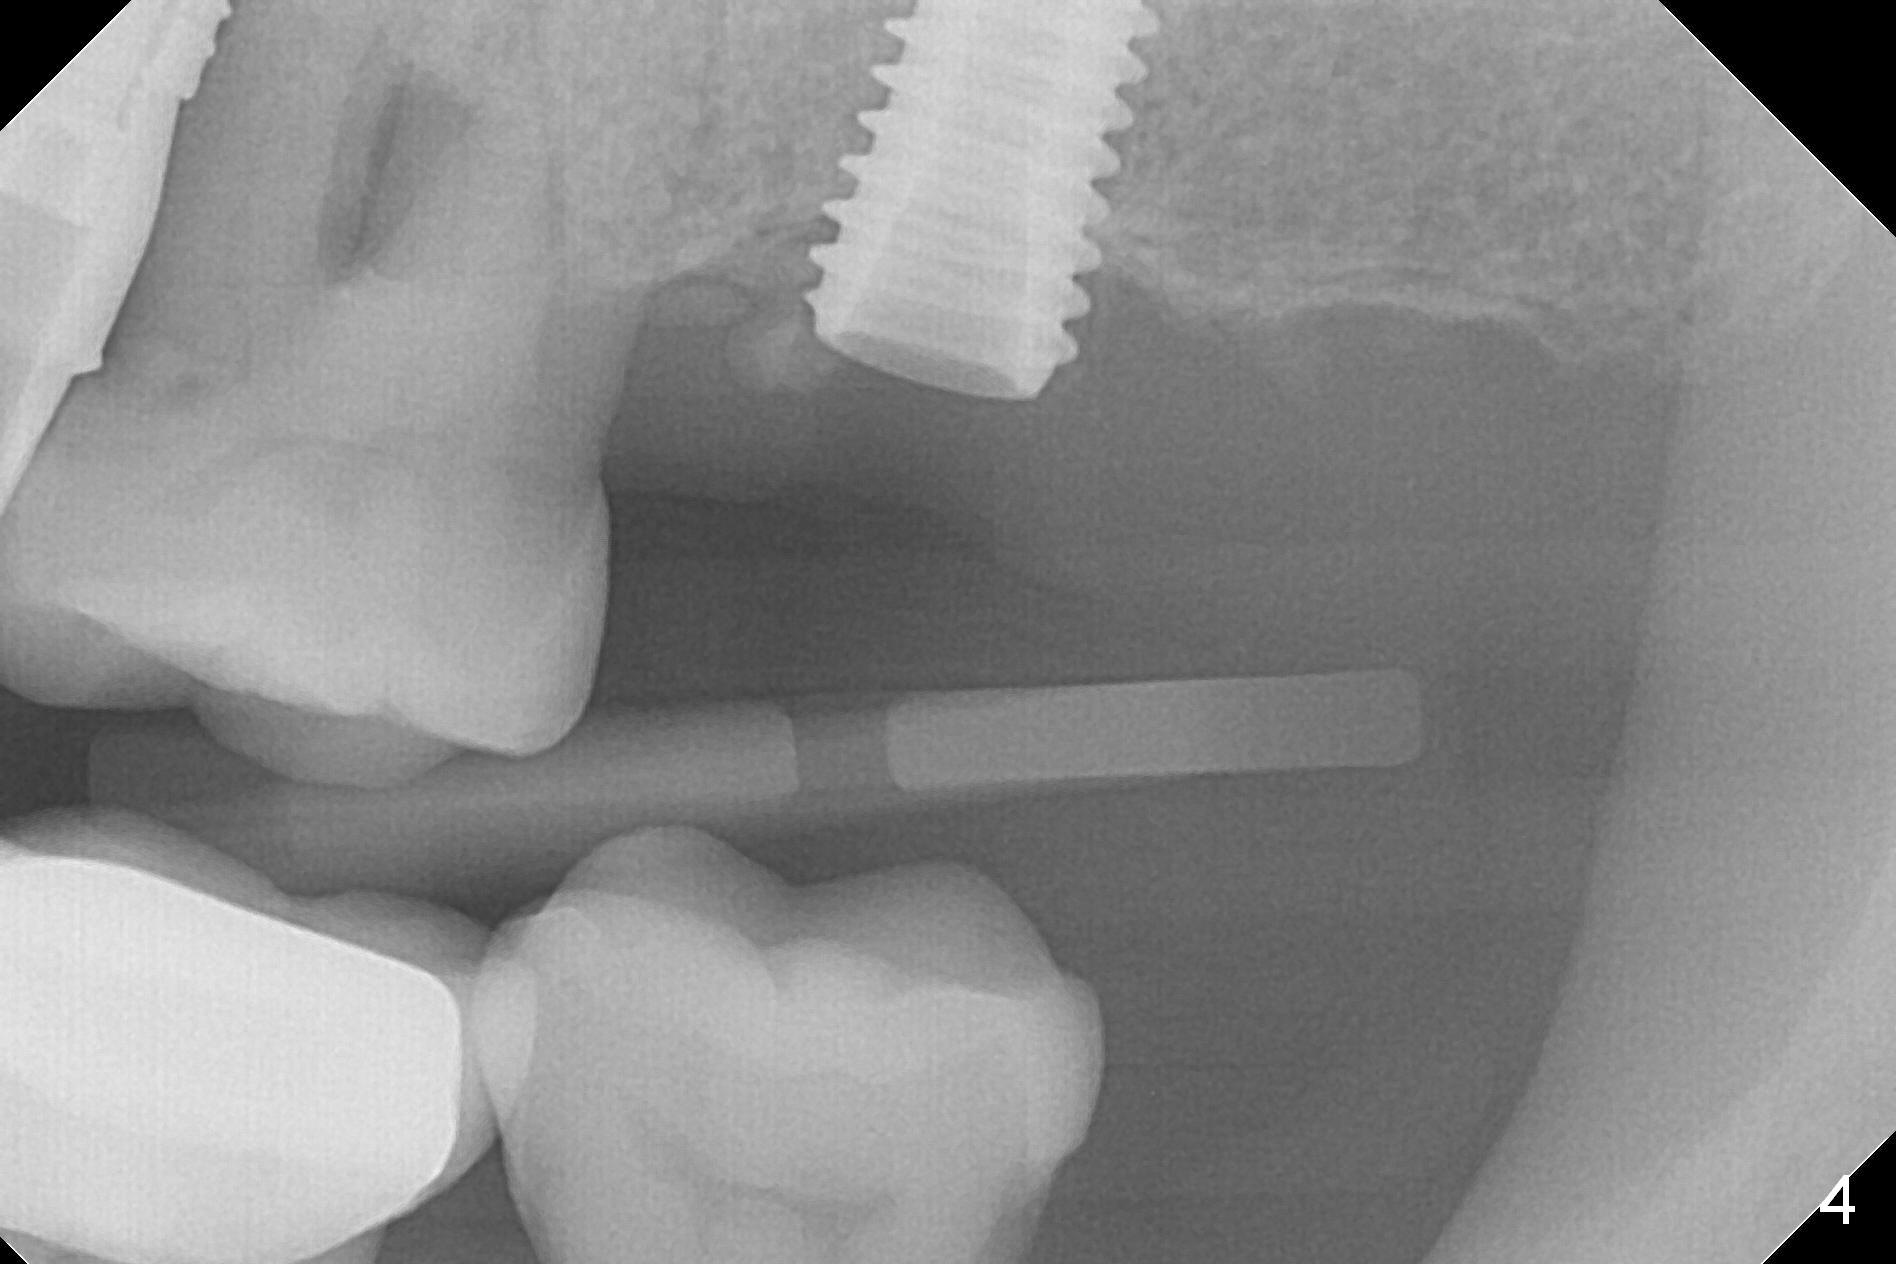

A 1.2 mm initial drill is used to start osteotomy at the site of #15 (Fig.1). After moving the osteotomy distally (with Lindamann bur), the osteotomy is enlarged by DIO Bone Expanders until 2.4/3.7 mm for 18 mm (gingival level) (Fig.2). Following the expander 3.0/4.4 mm, a 5x13 mm UF implant is placed supracrestal (Fig.3,4). After deepening the osteotomy with 3.8 mm drill for 3 mm, the implant is placed deeper by ~ 2 mm (Fig.5 arrow). Since the tooth #18 is supraerupted, a healing abutment (5.5x12(3) mm) is placed (Fig.6: H); the gingiva adapts to the abutment well. Suture is not necessary. The bone remains stable 2 and 4.5 months postop (Fig.7,8). Impression is taken. A crown is delivered nearly 6 months postop (08/07/2017). While there is minimal bone loss at #13 and 15 three years and 4 months post cementation, the tooth #14 and 18 are mobile (Fig.13,14, #13).